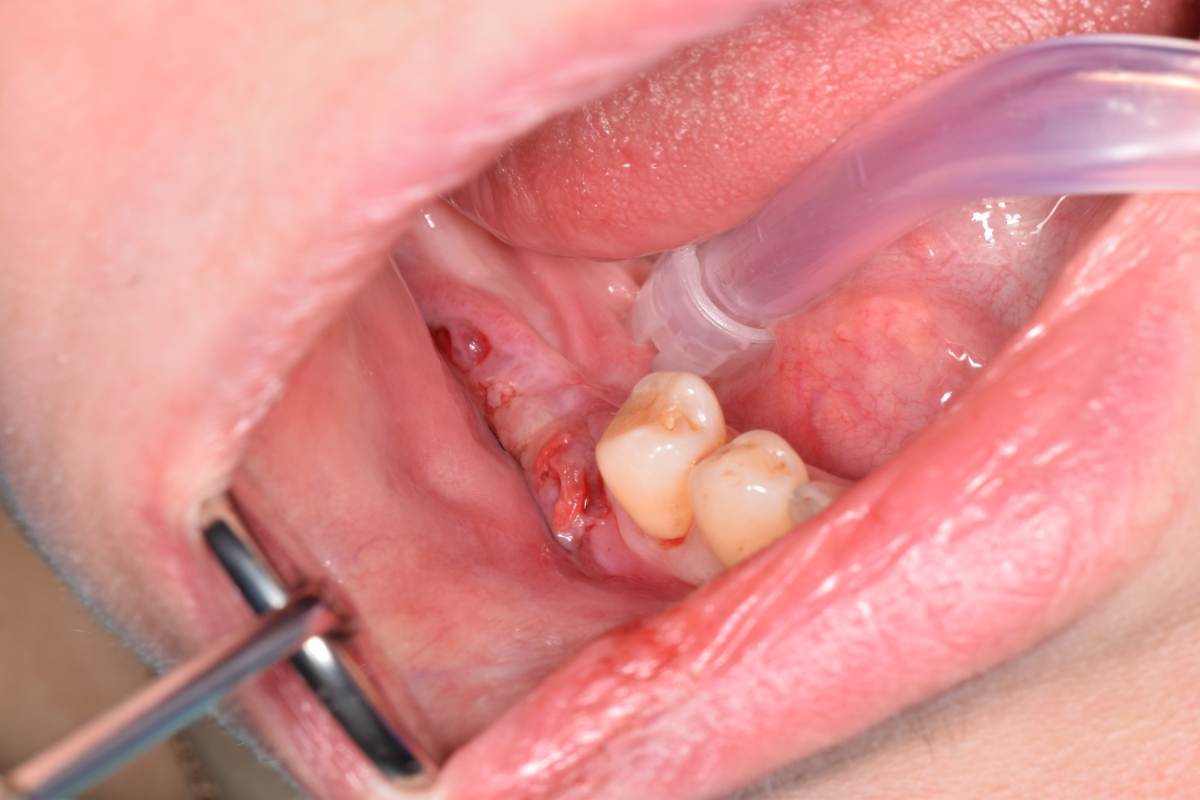

Да, фото есть. Но вспоминаю клин случай, там на первом этапе уже были проблемы.

СдТ по Едранову, видимо получил воспалительный процесс. В результате СДТ усело более чем на 50%.  Потом через 1.5 мес. открытие имплантов и ССТ. Некроз у одного импланта.Думаю связано с неполным ушиванием и ССТ с эпителием. Восстановление слизистой после некроза 2 мес и временное протезирование. Сейчас все выглядит достойно, но лишние нервы.

DSC_0905.JPG.d80af1f969af81edaec8fcb8e56af9dd.JPGDSC_0918.JPG.8053b3712edc335c60fe1603758c57c0.JPGDSC_0961.JPG.d7322462935746ed55516c1f2f016178.JPGDSC_1033.JPG.4e248180e536c308f43b21f90c8d7f39.JPGIMG_20250429_233136.jpg.c4afee93d2d2d38c68fd0335f7814cf2.jpgIMG_20250429_233013.jpg.58a7d5dc49b818431505d37c6561f01e.jpgDSC_0468(1)_d4542c.JPG.507134270c79baa6b79b4eb40f621175.JPG